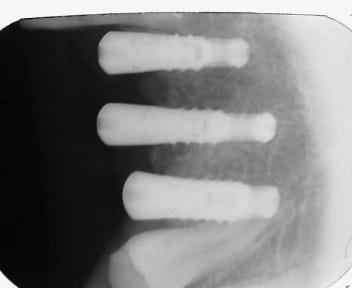

Le praticien qui a posé me dit que c'est un biotech : je ne trouve pas que la radio ressemble à la game biotech ... une explication ?

si, mais çà doit être un petit diamètre, en hex externe...

Ce qui m'interpelle c'est que je ne trouve pas d'implants biotech ressemblant a la radio

> Ce qui m'interpelle c'est que je ne trouve pas d'implants biotech ressemblant a

> la radio

c'est çà...

http://osseosource.com/dental-implants/product_info.php?manufacturers_id=144&products_id=1054

avec la vis de cicat...

ah oui...c'est un octagone externe et non un hexagone....

C'est un tissue level donc si tu mets le col lisse dans l'os ça cratérise, sinon perso je n'ai jamais eu de cratérisation avec ce modèle de bis (le bis conic par contre oui)